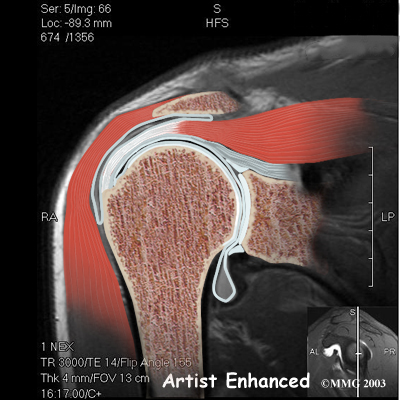

The rotator cuff connects the humerus to the scapula. The rotator cuff is formed by the tendons of four muscles: the supraspinatus, infraspinatus, teres minor, and subscapularis.

Rotator Cuff

Tendons attach muscles to bones. Muscles move the bones by pulling on the tendons. The rotator cuff helps raise and rotate the arm.

As the arm is raised, the rotator cuff also keeps the humerus tightly in the socket of the scapula, the glenoid. The upper part of the scapula that makes up the roof of the shoulder is called the acromion.

A bursa is located between the acromion and the rotator cuff tendons. A bursa is a lubricated sac of tissue that cuts down on the friction between two moving parts. Bursae are located all over the body where tissues must rub against each other. In this case, the bursa protects the acromion and the rotator cuff from grinding against each other.